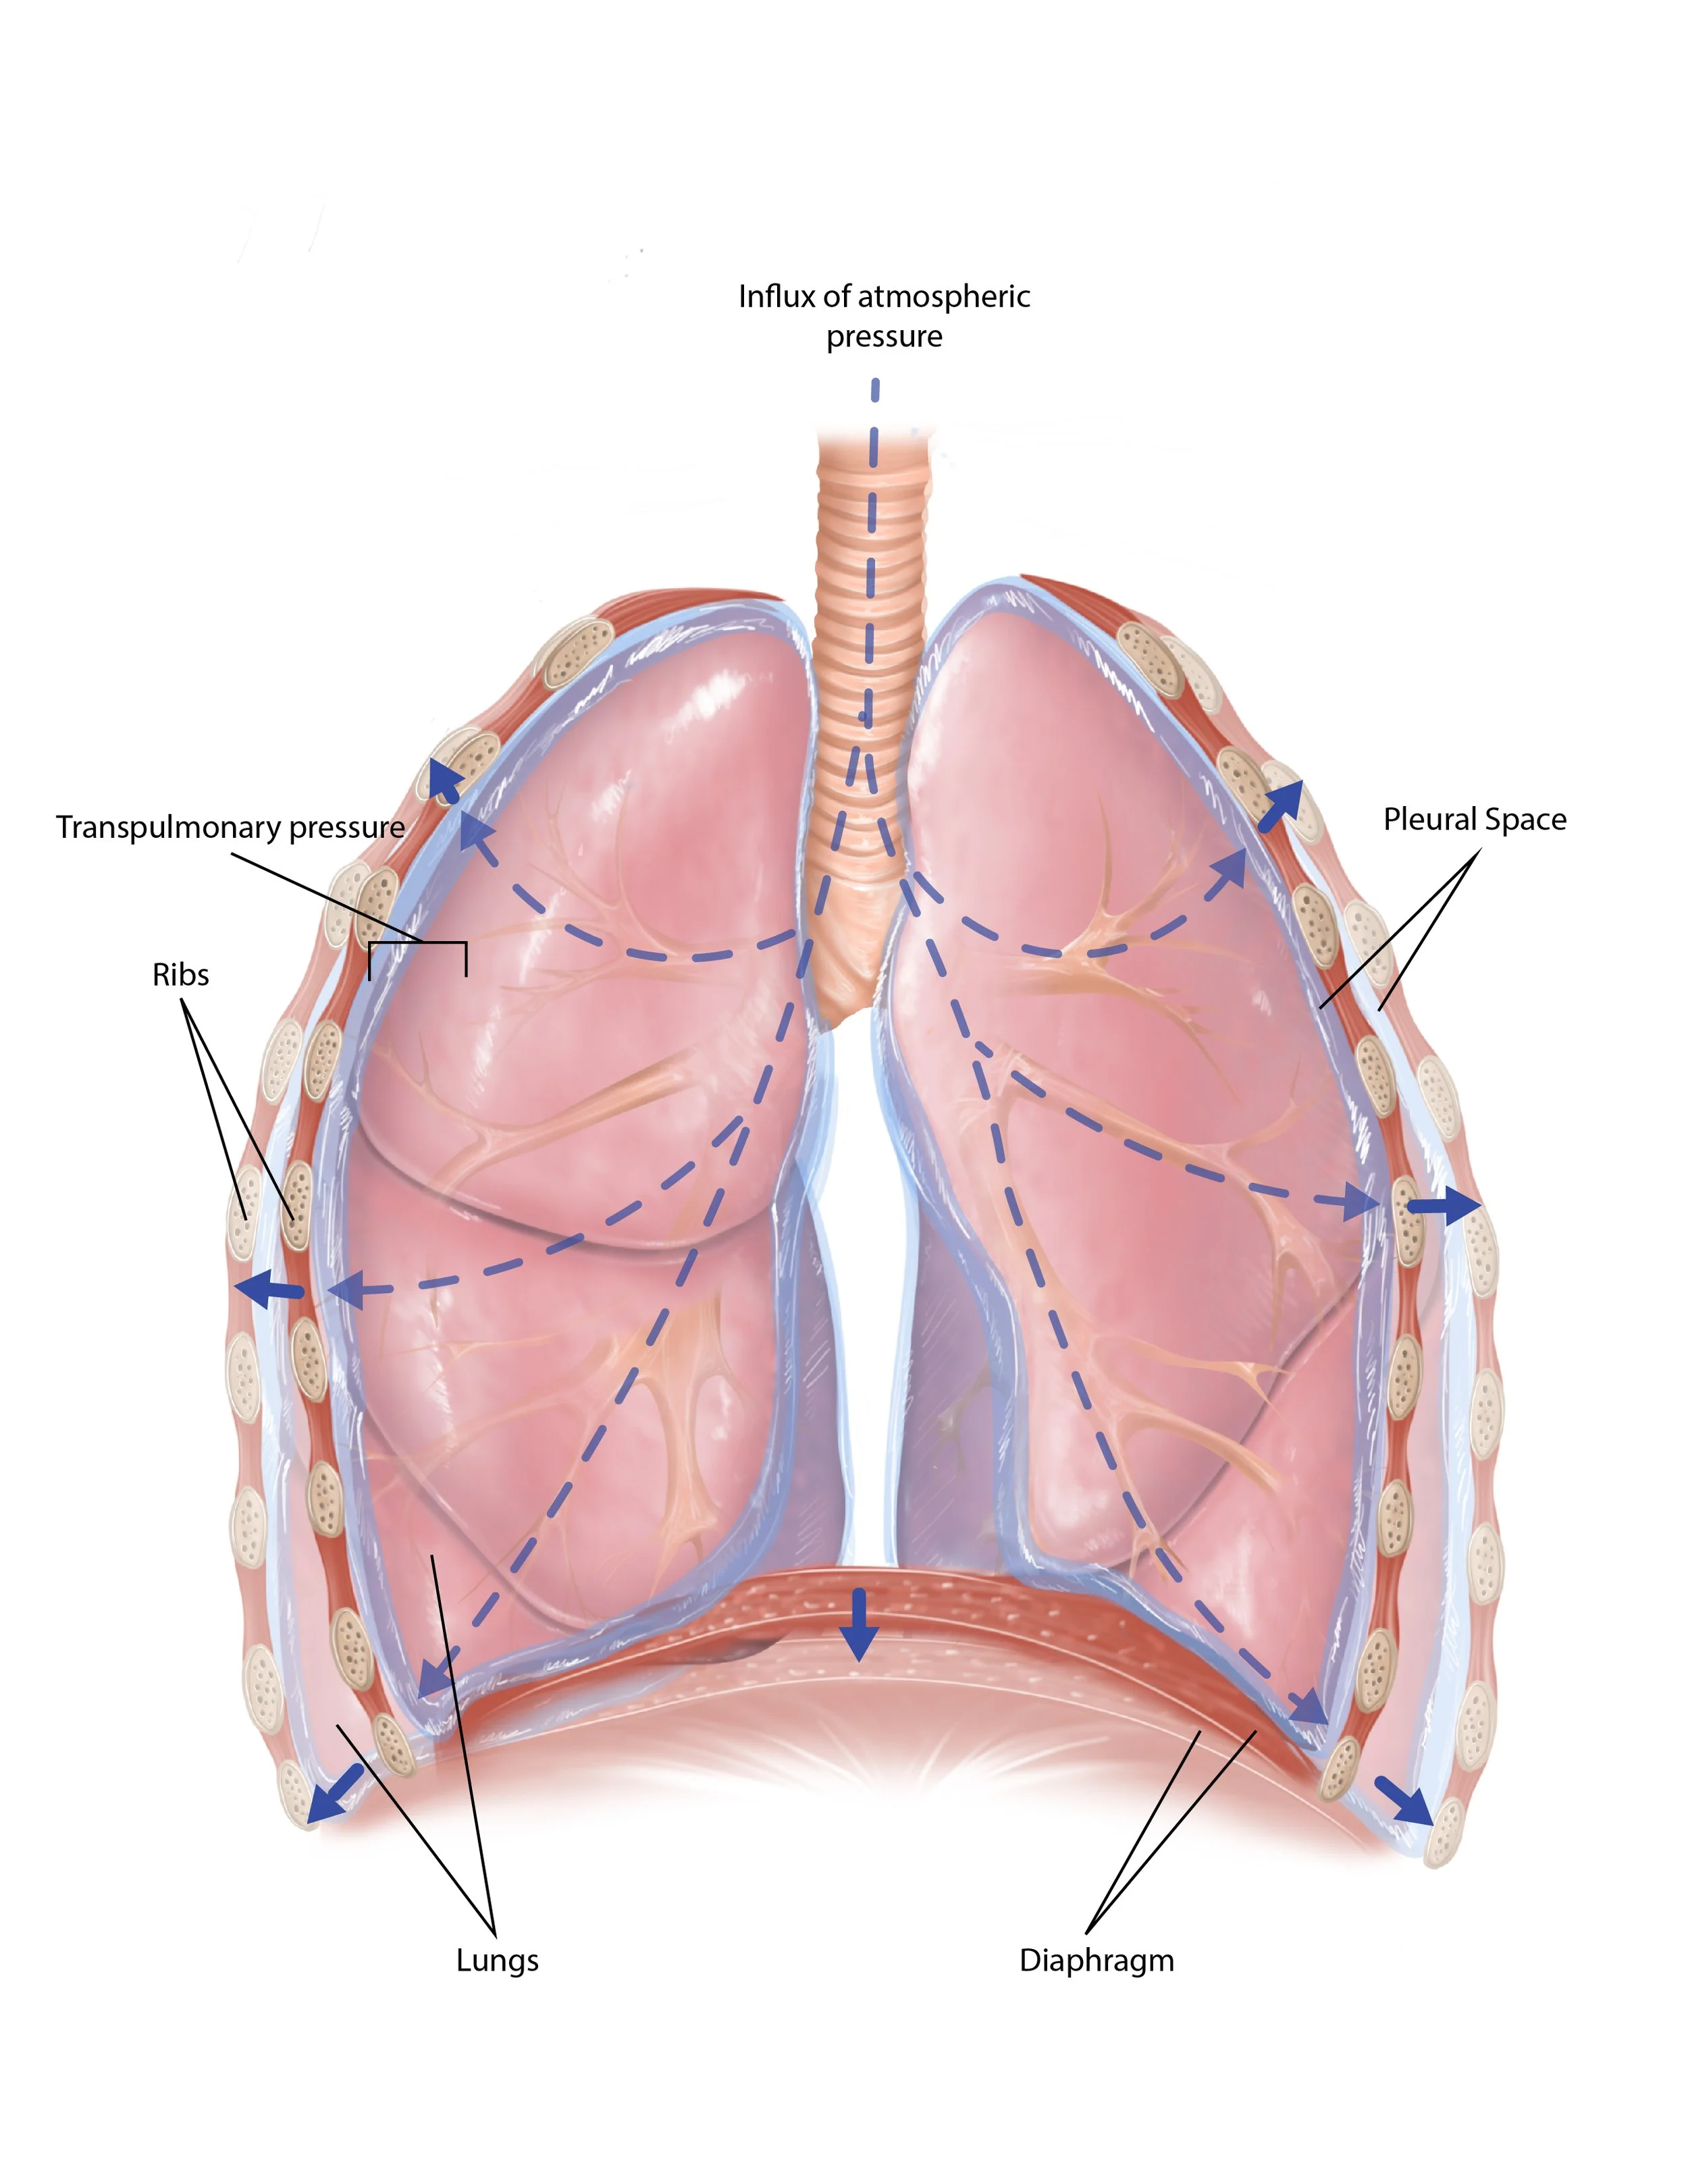

Respiratory Series: Particle Deposition

Illustration series created for Rochester Institute of Technology’s Personalized Healthcare Technology 180. This series defines the anatomy of the lungs, the physiological changes that occur during breathing, and describes the particle deposition within the lungs.